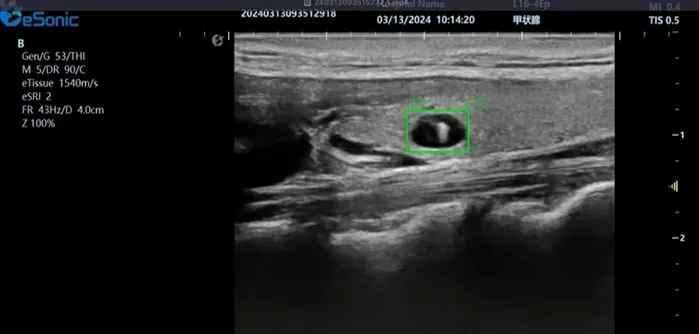

银河官网医疗(ESI)表示,其最新的人工智能功能可以帮助到医疗机构的工作效率,功能包括,实时、动态、快速自动识别病灶,良恶性病灶概率预测,甲状腺结节和乳腺的二维灰阶动态自动实时检测需求,提供多个结节动态检测轮廓框。实时获取多幅具备临床特征(大小、属性等)的结节切面,同时提供当前切面所示结节的结节大小、属性特征、TI-RADS 分级。

对于甲状腺结节相关的自动检测功能,甲状腺结节病灶检出率≥95%,良恶性分类灵敏度≥90%、良恶性分类特异度≥85%。